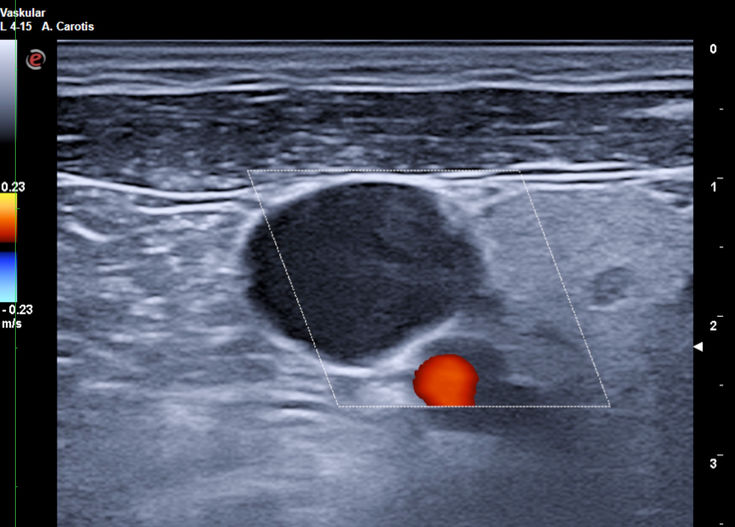

Goldstandard ist die Punktion der rechten Vena jugularis/anonyma supraklavikulär nach oder unter sonographischer Kontrolle. Die Sonographie muß Lagevarietäten klären und Thrombosen nach früherer Katheterisierung ausschließen.

Die in der Anästhesie verbreitete Punktion der distalen Vena jugularis ist komplikationsträchtig und sollte vermieden werden. Normalerweise liegt die Vena jugularis lateral der A. carotis.

Bei der schädelnahen Punktion muß der Kopf nach links gedreht werden, weil sonst das Kinn im Weg ist. Dadurch rotiert die Vene vor die Arterie und das Lumen wird schlitzförmig.